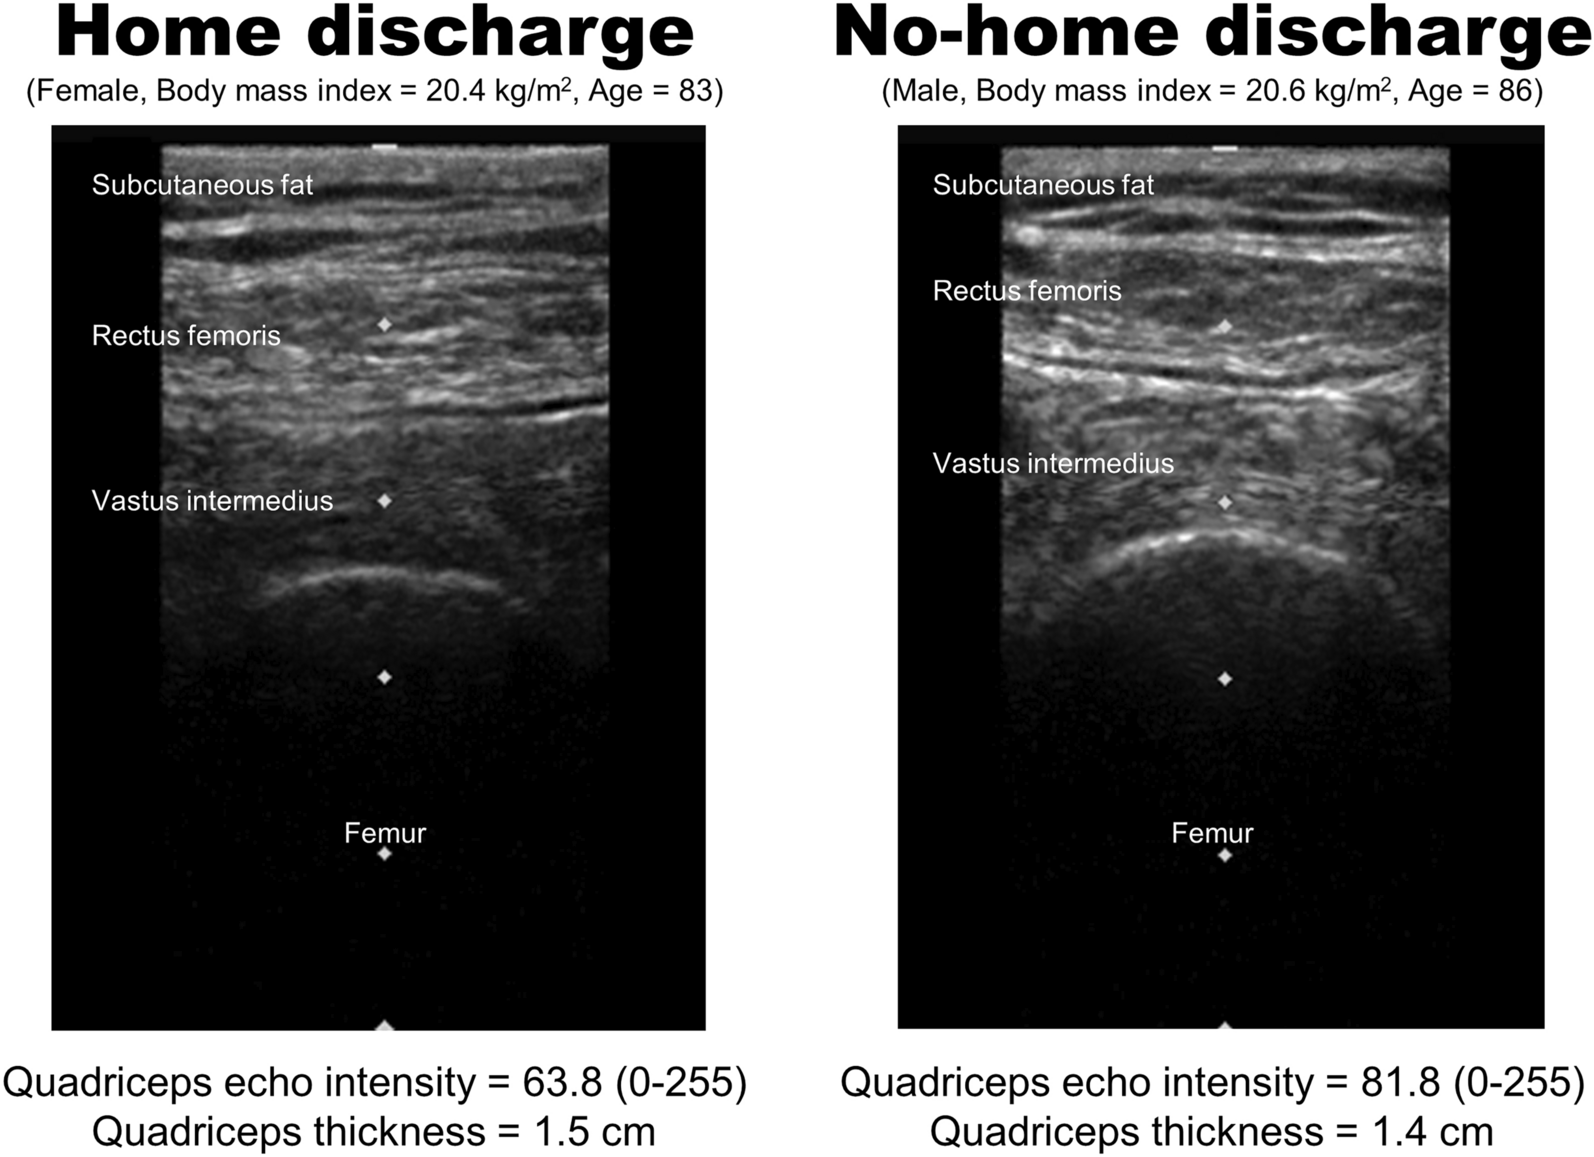

Typical ultrasound images of patients with home discharge and no-home discharge.